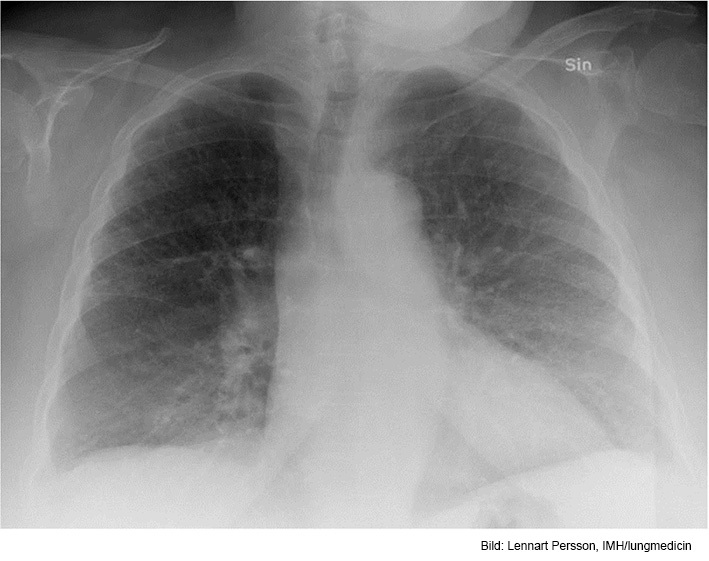

Vad visar röntgen?

Bild förenlig med t ex KOL

Gles kärlteckning, särskilt apikalt (emfysem ev) och antytt avplanade diafragmakupoler, särskilt höger, förenligt med KOL. Något förstorat hjärta men ingen stas.

Litet infiltrat basalt höger